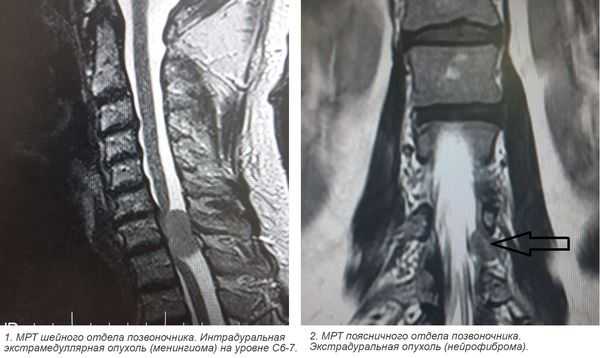

- экстрадуральная опухоль – очаг над областью твердой мозговой оболочки;

- интрадуральная – опухоль под твердой оболочкой;

- интрамедуллярная – растет внутри спинного мозга, происходя из его клеток.

Современная клиническая нейрохирургия и неврология используют в своей практике несколько основных классификаций спинномозговых новообразований. По отношению к спинному мозгу опухоли подразделяют на экстрамедуллярные (80%) и интрамедуллярные (20%). Опухоль спинного мозга экстрамедуллярного типа развивается из тканей, окружающих спинной мозг. Она может иметь субдуральную и эпидуральную локализацию. В первом случае новообразование изначально находится под твердой мозговой оболочкой, во втором — над ней. Субдуральные опухоли в большинстве случаев имеют доброкачественный характер. 75% из них составляют невриномы и менингиомы. Невриномы возникают в результате метаплазии шванновских клеток задних корешков спинного мозга и клинически дебютируют корешковым болевым синдромом. Менингиомы берут свое начало в твердой мозговой оболочке и крепко срастаются с ней. Экстрадуральные опухоли имеют весьма вариативную морфологию. В качестве таких новообразований могут выступать нейрофибромы, невриномы, лимфомы, холестеатомы, липомы, нейробластомы, остеосаркомы, хондросаркомы, миеломы.